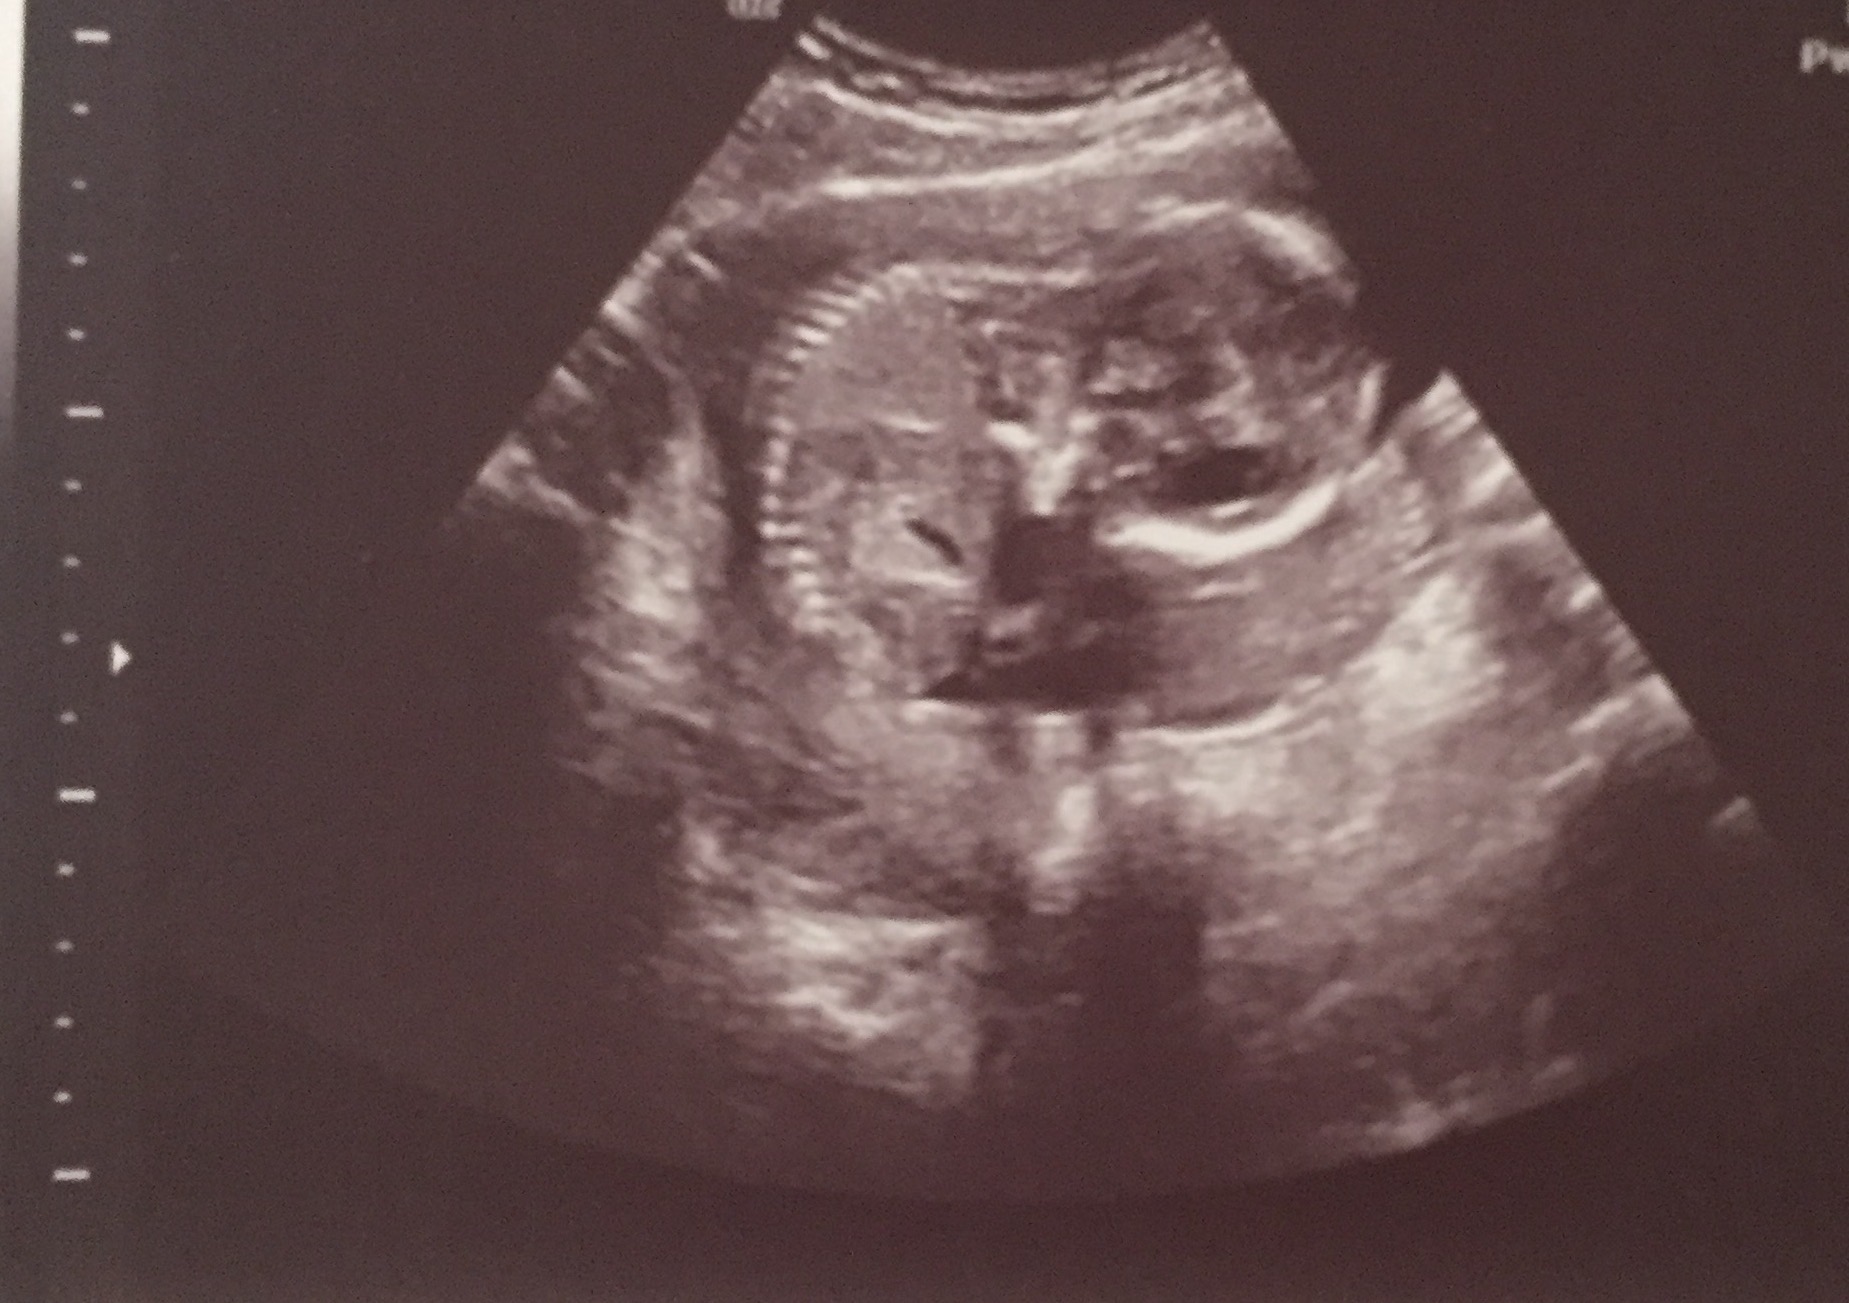

I had an elective 2d/4d ultrasound done at 16 weeks and 3 days to determine the gender of my baby. The baby wasn't all that cooperative and had the umbilical cord between its legs. It moved it's legs for a second and the ultrasound technician said that she saw the "hamburger buns" (labia). She also said that she saw the three white lines of the vaginal bones multiple times and that she felt confidant it was a girl. However, she could not get me a clear picture of the genitals in 3d because the baby would not move it's leg again to give a clear view of it's parts. She took this picture (1st picture) in 2d of what is the supposed white lines. I am just looking for opinions on whether this looks like a baby girl or if it could be a boy because I don't want to tell my whole family and then be surprised at my 19 week scan when they say it's a boy. The pictures are big, I'm not sure how to make them smaller.

Attachment 35758